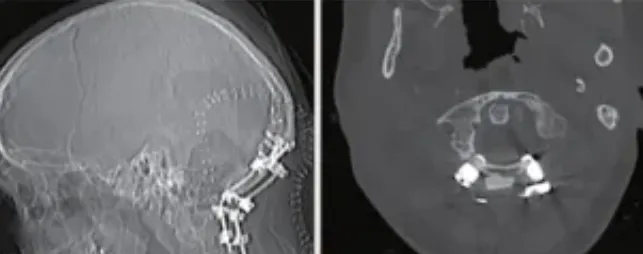

▼最后,由于右侧枕髁完全被肿瘤侵犯,因此,在肿瘤切除后,还需要进行手术融合稳定。